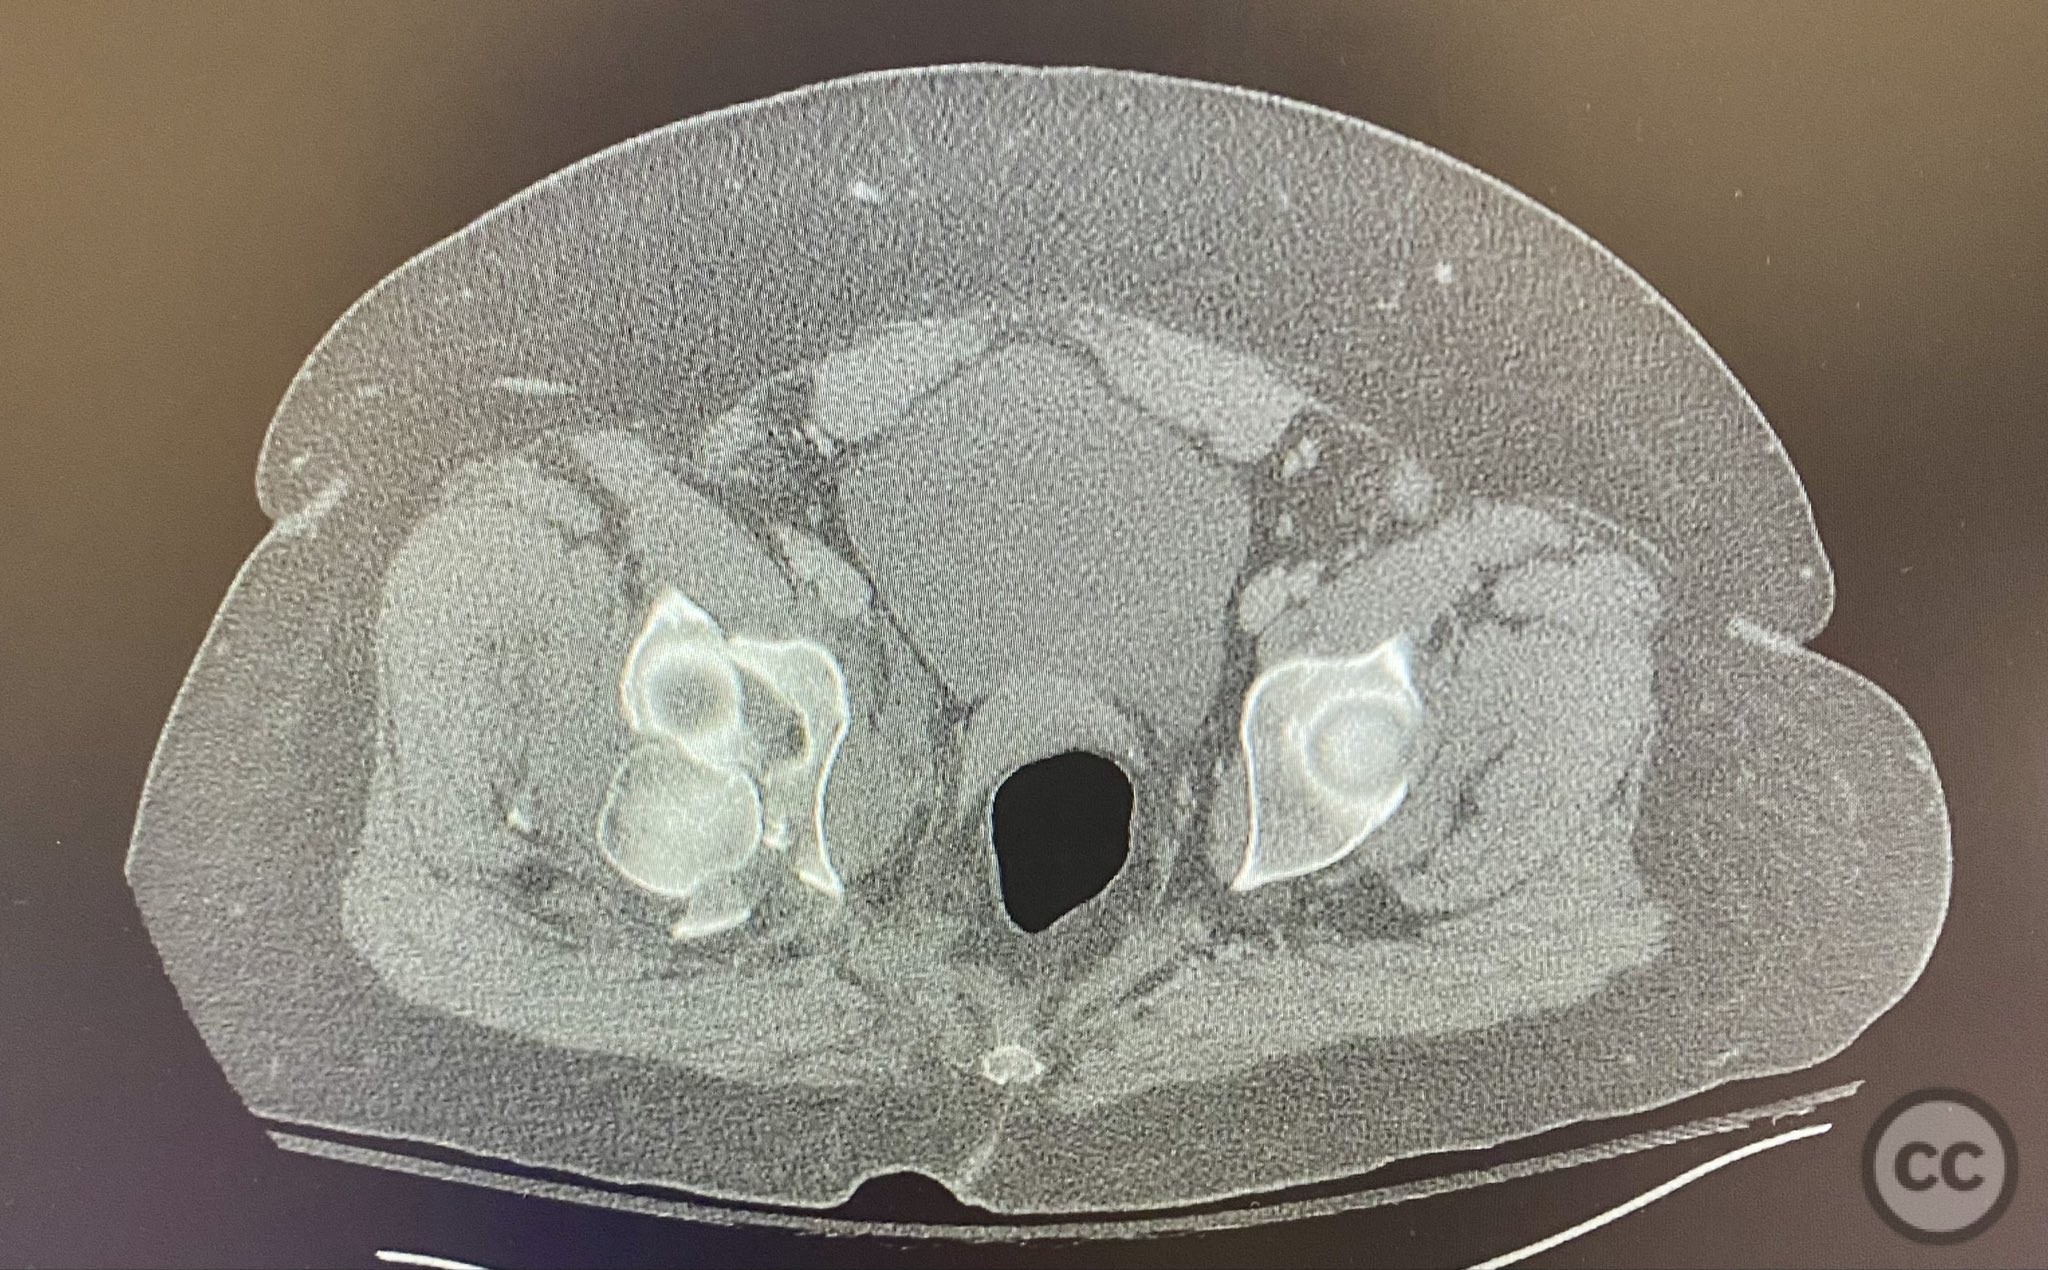

Clinical and radiological findings:  A high-speed motor vehicle collision resulted in a closed transverse acetabular fracture with associated comminuted posterior wall (PW) fracture-dislocation. The femoral head exhibited impaction and comminution, with local cancellous bone crushed and the femoral head itself also sustaining compressive injury from the denser acetabular bone. Neurovascular examination was unremarkable. Initial CT imaging delineated the acetabular fracture planes, displacement, comminution of the posterior wall, femoral head impaction, and absence of soft tissue attachment to the caudal PW fragment.